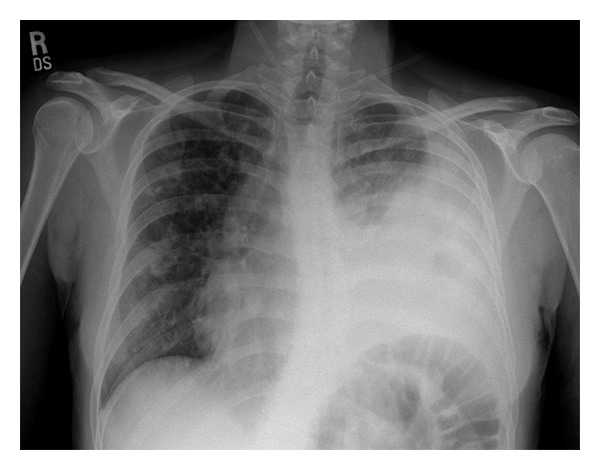

Input 3: What is seen in the X-ray and what should be done?

Image:

• Visual Med-Alpaca: Bilateral infiltrates and bilateral pleural effusion seen in a chest x-ray may indicate a respiratory infection or other respiratory conditions such as pneumonia pulmonary edema, or pleural effusion, it is important to consult a medical professional for a proper diagnosis and treatment plan.

• VQA Medical Model: the decubitus

• Automatic Radiology Report Generation (Image-only): near complete opacification of the left hemi thorax with only a small amount of residual aerated lung in the left upper lobe .

• ChatGPT (GPT-3.5-Turbo) + Automatic Radiology Report Generation (Image-only): Opacification of the lung on an X-ray indicates that there is an abnormality in the lung tissue. In this case, the near-complete opacification of the left hemithorax with only a small amount of residual aerated lung in the left upper lobe suggests that there is likely a significant pathology present in the left lung. Possible causes of this finding include pneumonia, lung abscess, tumor or mass, or pleural effusion (fluid accumulation around the lung). It is important to determine the underlying cause of this finding as soon as possible. A follow-up diagnostic workup may include a CT scan of the chest, sputum culture, bronchoscopy, and/or a biopsy of any suspicious areas in the lung. The appropriate treatment will depend on the underlying cause, but it may include antibiotics, drainage of any fluid collections, or surgery to remove any masses or tumors. Prompt evaluation and treatment are necessary to prevent complications and improve outcomes.